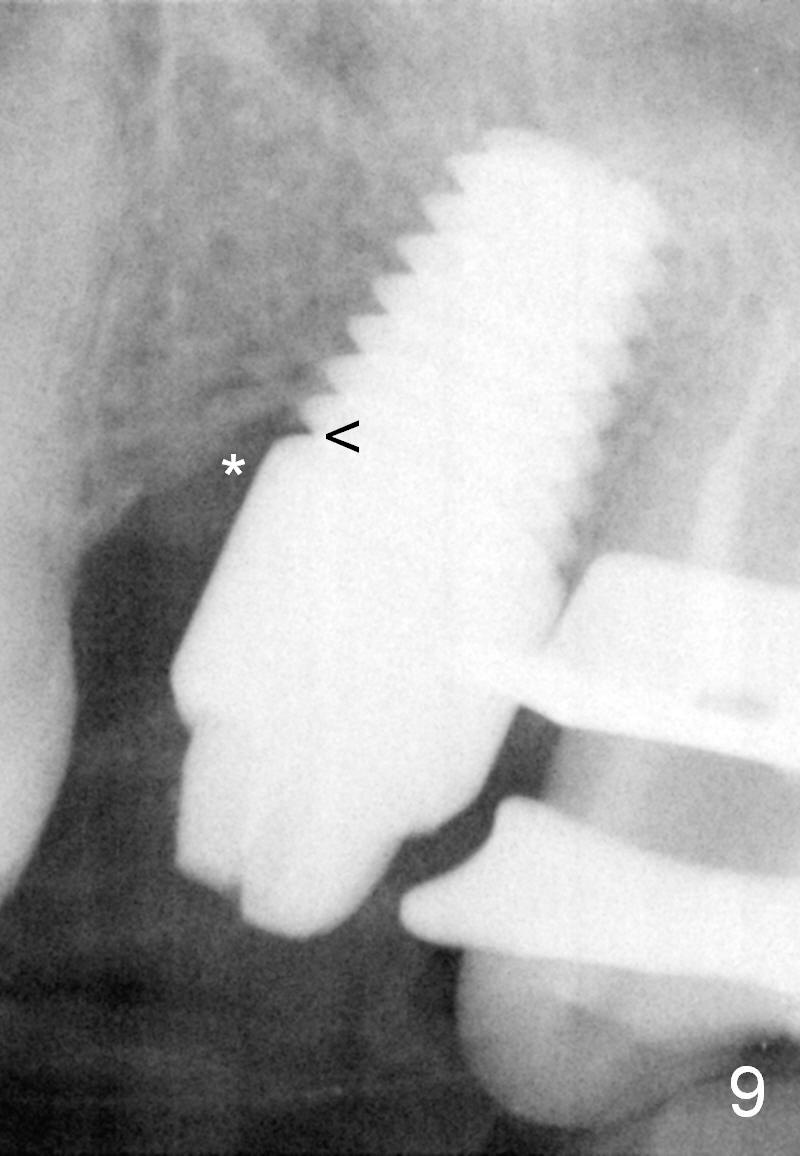

Twenty-one months postop, the patient returns for #15 RCT. PAs show that although there is a narrow space in the original mesial socket (Fig.9 *), the 1st thread space is partially obliterated with the bone (<). In contrast, the distal 1st thread space is completely obliterated (Fig.10 >). After the RCT, impression is taken for #14 and 15. Although there is no sign of periimplantitis, the 7x14 mm implant looks too large for the site with possible buccal thread exposure 4 years 9 months post cementation (Fig.11). To reduce complications, a much small fixture will be at #30.